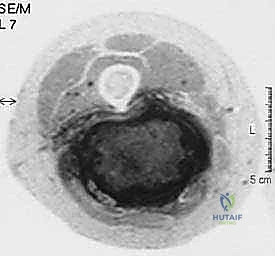

1. التصوير بالرنين المغناطيسي (MRI)

يُعد الرنين المغناطيسي بالصبغة المعيار الذهبي (Gold Standard) لتشخيص أورام الأنسجة الرخوة. يوفر صوراً ثلاثية الأبعاد وعالية الدقة تفصل الورم عن العضلات السليمة، وتوضح بدقة متناهية علاقة الورم بالعصب الوركي والأوعية الدموية الرئيسية (الشريان والوريد الفخذي العميق).

نصيحة طبية من الأستاذ الدكتور محمد هطيف: "أي كتلة أو تورم في الأطراف يتجاوز حجمها 5 سنتيمترات (حجم كرة الجولف)، أو تستمر في النمو، أو توجد عميقاً تحت الجلد، يجب تقييمها فوراً من قبل طبيب متخصص في جراحة العظام والأورام. التشخيص المبكر هو مفتاح النجاة."